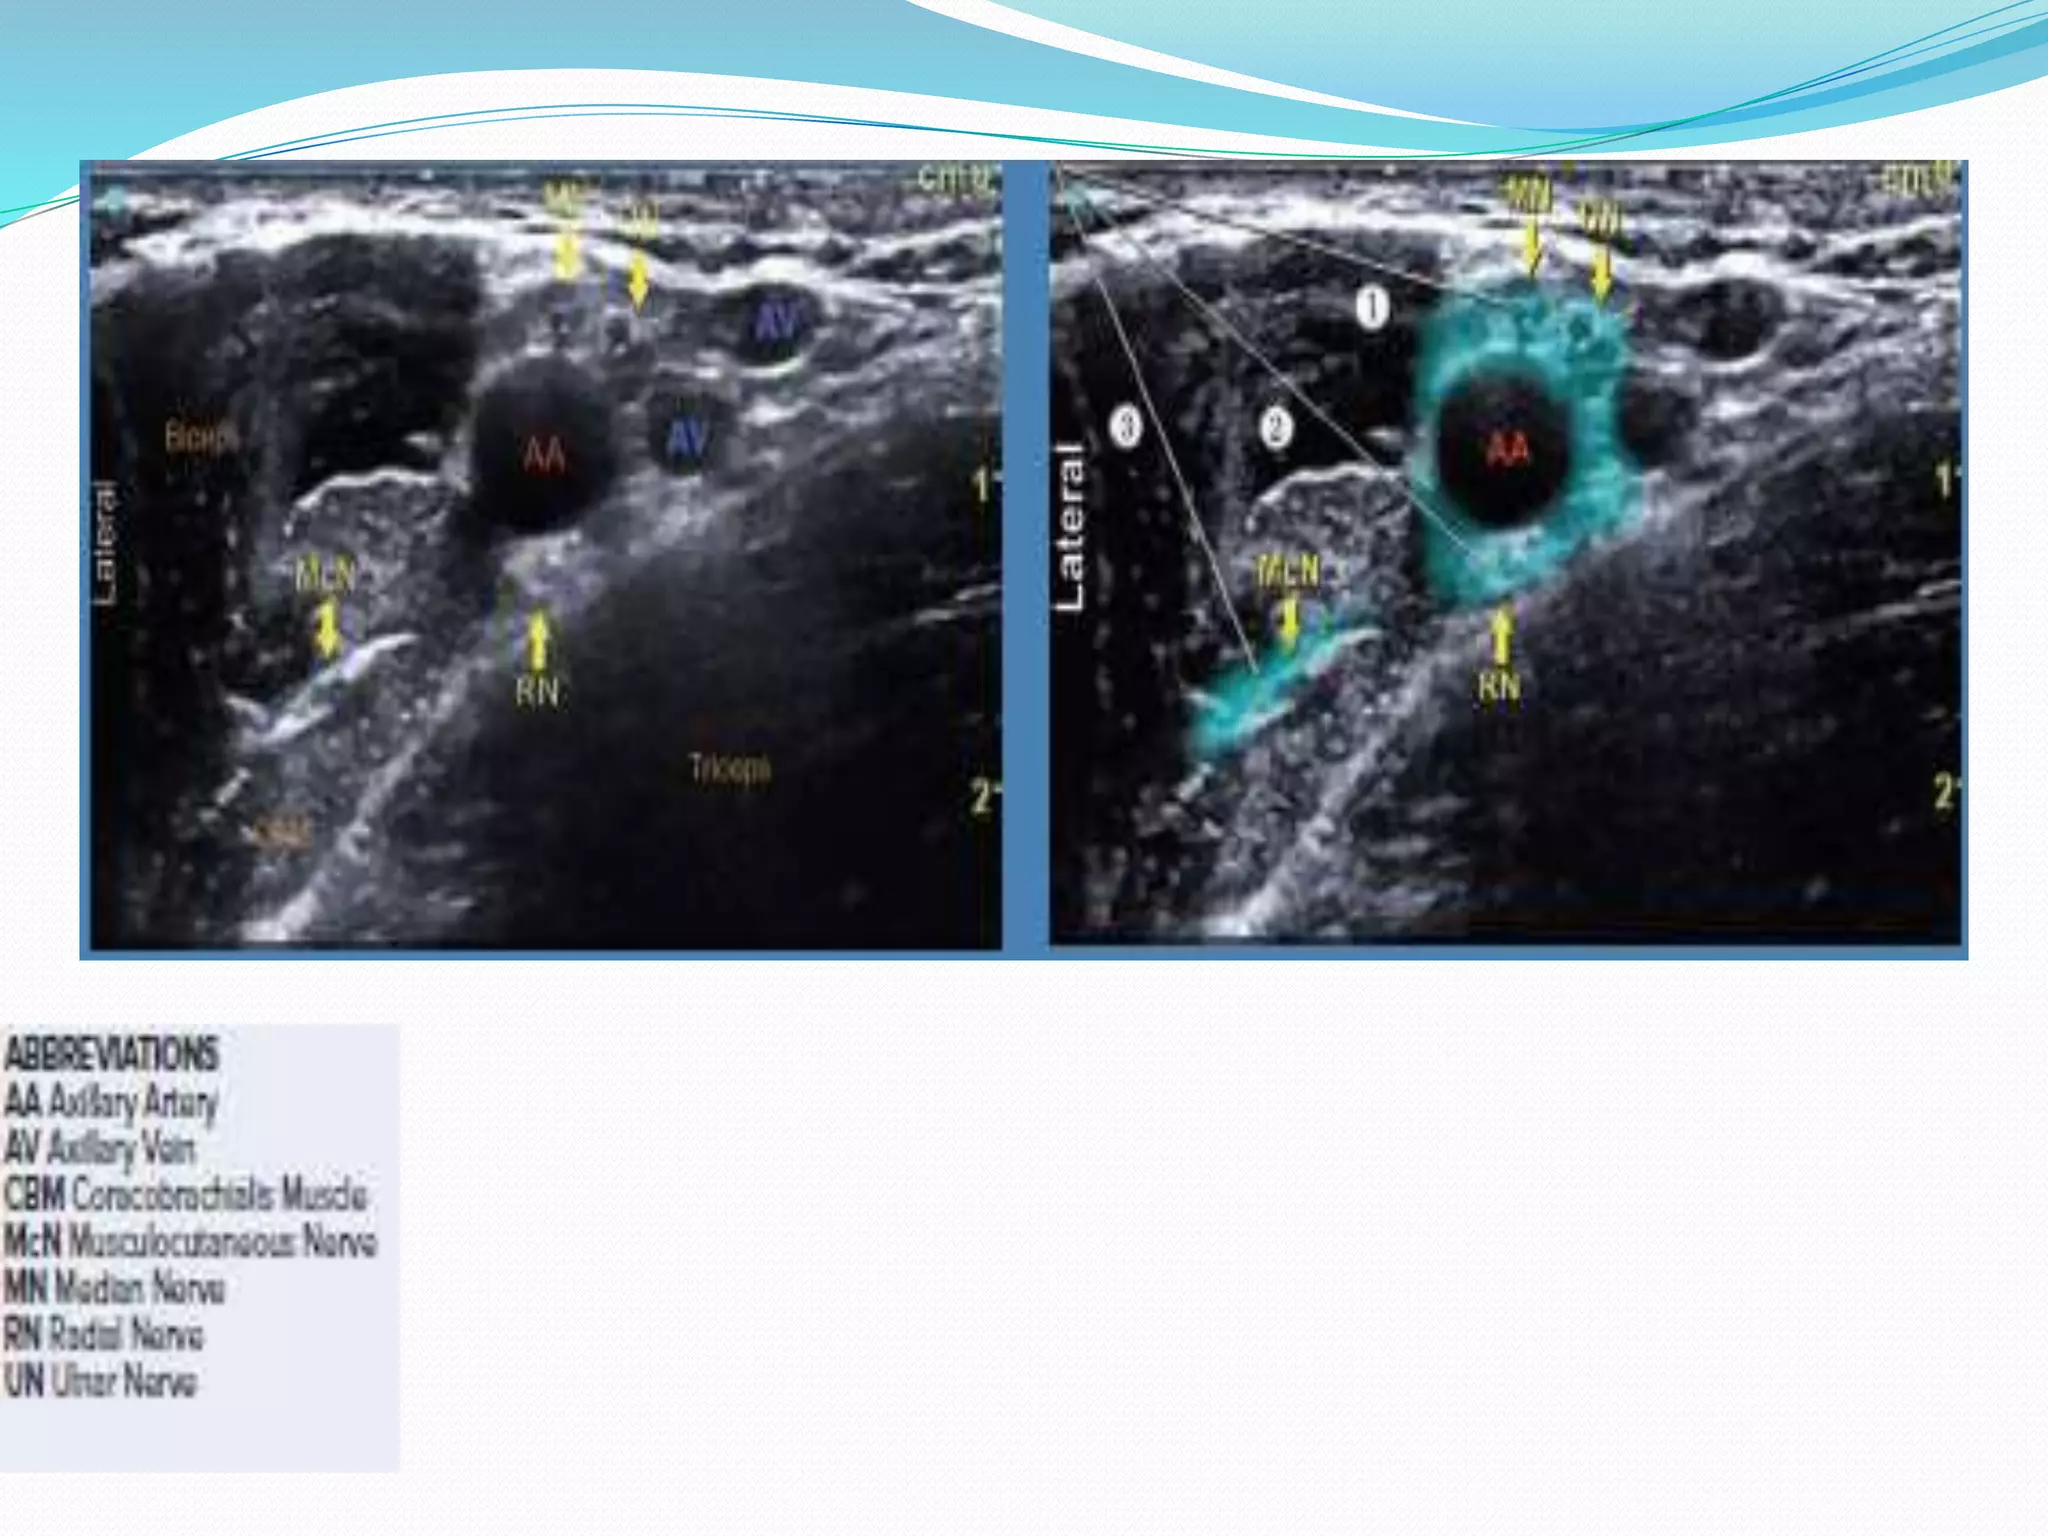

This document provides an overview of brachial plexus anatomy and techniques for brachial plexus nerve blocks. It begins with a description of the brachial plexus formation from cervical and thoracic nerve roots and its branching pattern. Four main approaches for brachial plexus nerve blocks are described: interscalene, supraclavicular, infraclavicular, and axillary. Details are provided on the anatomy and techniques for performing interscalene and supraclavicular brachial plexus blocks. Ultrasound guidance is discussed as an advancement which allows real-time visualization of needle and nerve. Complications are also summarized.